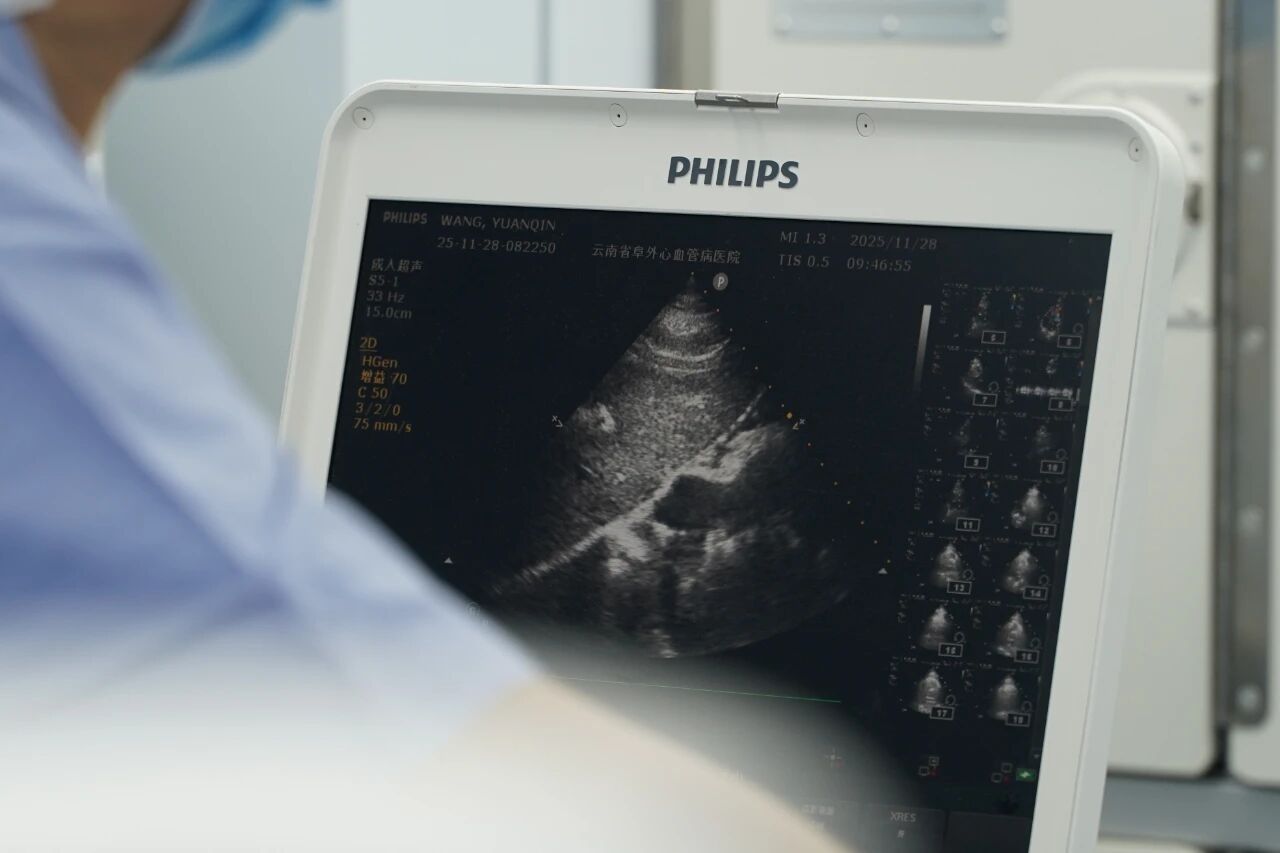

走进这辆长12米、宽4米的白色移动手术车,可谓是“内有乾坤”——车内灯火通明,略显紧凑的空间里,数字化血管造影机、麻醉机等设备一应俱全。医护人员身着无菌手术衣,正全神贯注地为患者实施介入手术,仪器屏幕上清晰显示着心脏结构,主刀医生在超声引导下精准操作,整个手术过程紧张而有序。